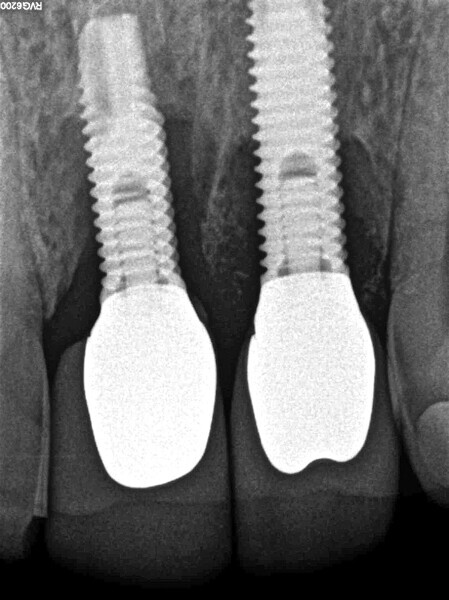

Peri-implantitis therapy